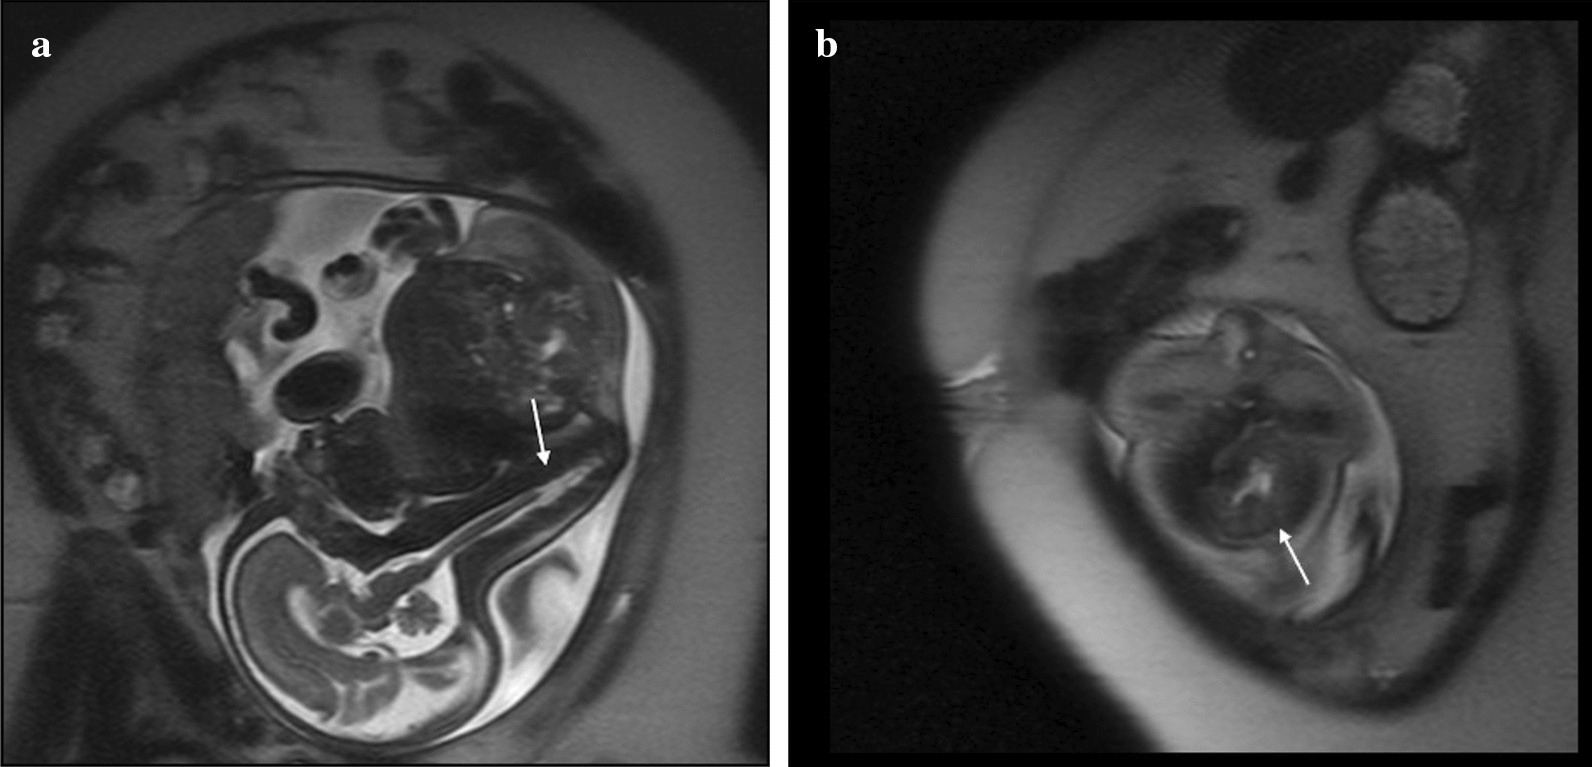

A 29-year-old primigravida Caucasian female with a past medical history significant for short stature, tobacco use, and poorly controlled pregestational type 2 diabetes mellitus (DM) presented to clinic for routine antenatal care. She was first diagnosed with diabetes mellitus at age 22 and managed with metformin prior to pregnancy with a history of poor glycemic control. She was transitioned to glyburide 5 mg twice daily by her obstetrician and subsequently increased to 10 mg twice daily secondary to continued elevated blood glucose levels (fasting ranged from 78 to 113 mg/dl and 2-hour post prandial ranged from 97 to 332 mg/dl). At 13 and 3/7 weeks of pregnancy, the patient was admitted for tighter blood glucose management, initiation of insulin, and a dietician consult to achieve improved control of glucose levels. A baseline hemoglobin A1c was obtained on admission and noted to be high at 8%. Previous maternal hemoglobin A1c levels were not reported. Antenatal fetal ultrasound at 22 weeks was notable for severe sacral agenesis, bilateral renal pelvis dilatation, single umbilical artery, and findings suggestive of pulmonary hypoplasia. The patient was referred to a tertiary care fetal and neonatal medicine center in the USA for further evaluation, and fetal magnetic resonance imaging (MRI) was recommended for confirmatory testing. Fetal MRI at 29 weeks gestation showed absence of the lower two-thirds of the spine with corresponding spinal cord abnormality compatible with type 1 caudal regression syndrome (Fig. 1a) with noted horseshoe kidneys (Fig. 1b). No fetal cardiac anomaly was detected. Fetal anomalies were likely secondary to poorly controlled diabetes during early pregnancy. There was no significant family history.

Fig. 1.

A Fetal magnetic resonance imaging at 29 weeks gestation. Sagittal spine T2 Haste sequence on the fetal MRI shows absence of the lower two-thirds of the spine (arrow) and spinal cord abnormality in the fetus. B Fetal magnetic resonance imaging at 29 weeks gestation. Coronal spine T2 Haste sequence shows horseshoe kidneys (arrow)

Based on the position of the conus, patients with caudal regression syndrome are classified into two types [3]. Type 1 is the more severe form of caudal dysgenesis with a club-shaped, high-lying conus that terminates above the lower border of the L1 vertebrae. Type 2 caudal regression syndrome is less severe with a low-lying, tapered conus that terminates below the lower border of the L1 vertebrae [3]. The presented case showed absence of the lower two-thirds of the spine with the caudal cord terminating at the thoracic spine level on the fetal MRI consistent with type 1. It is important to determine corresponding soft tissue and visceral abnormalities associated with caudal regression syndrome to assess severity of disease and guide treatment planning. In our case, the extent of the syndrome was severe, with the fetal and postmortem MRI showing multiple associated abnormalities including decreased number of vertebrae, horseshoe kidneys, and fusion of the iliac wings. No cardiac anomalies or facial dysmorphisms were noted in this small-for-gestational-age infant, although the lower limbs were noted to be small with a talipes equinovarus deformity of the left lower extremity.